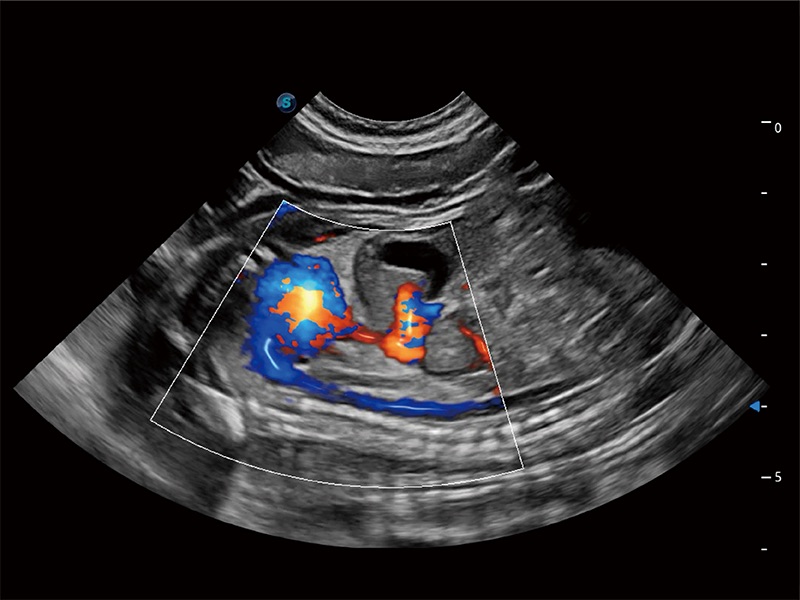

在傳統(tǒng)二維血流成像的基礎(chǔ)上,呈現(xiàn)血流的立體感,具有動(dòng)感的生命力之美。即便是微小的血管也能輕松應(yīng)對(duì),提高了血流的視覺(jué)敏感性。

非線性融合造影成像充分利用諧波和基波信號(hào),為難以觀察的血流進(jìn)行增強(qiáng)顯像??捎糜诰€陣、凸陣、微凸陣、相控陣探頭。